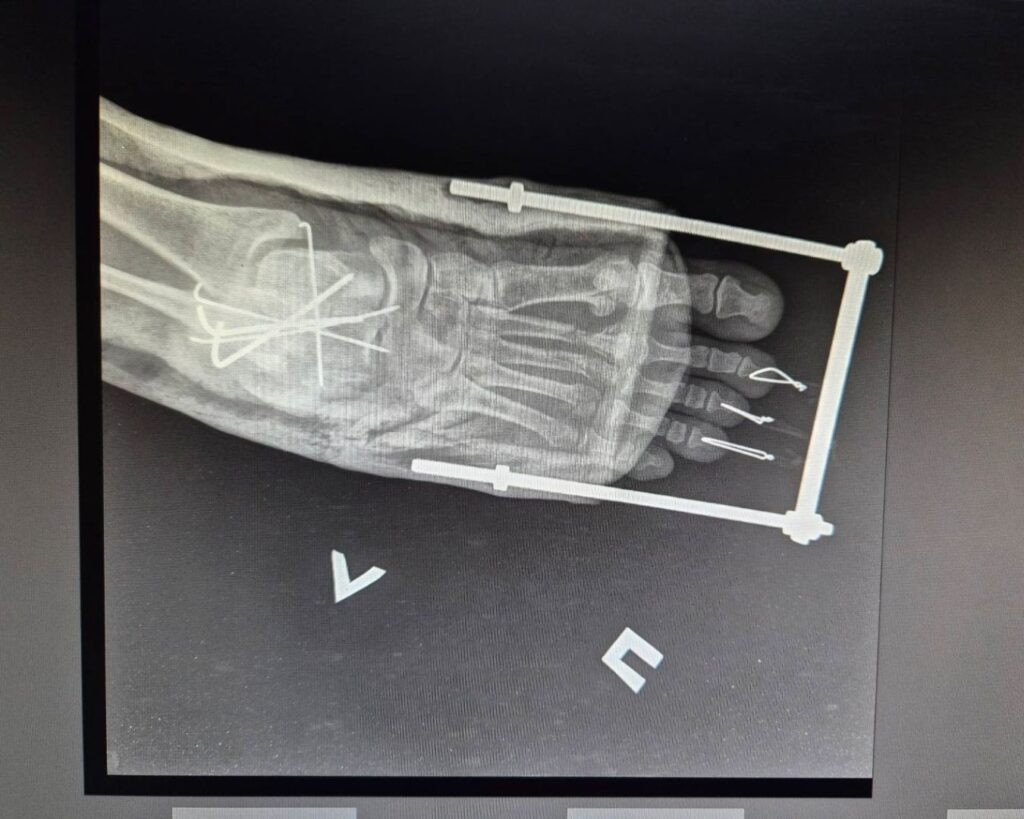

« L’une des patientes est une professionnelle de santé. Elle rentrait chez elle après le travail lorsque le drone a frappé le bus », explique Olha Severyn, anesthésiste de MSF à l’hôpital de Kherson. « Elle a subi de graves blessures aux jambes et aux pieds. Nous l’avons anesthésiée et opérée. » Une autre patiente, souffrant d’une grave fracture à la jambe et ayant perdu beaucoup de sang, a été traitée dès son arrivée. Les deux femmes sont actuellement dans un état stable.